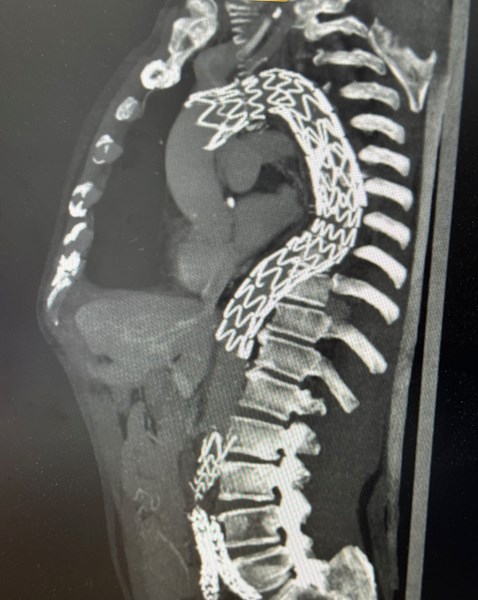

Иванко постъпва в лечебното заведение в условия на спешност, с оплаквания от силна болка в областта на корема и ляво подребрие. Насочен е от друго лечебно заведение, където е извършен скенер с контрастна материя и е установена голяма торакоабдоминална аневризма със задържано разкъсване в областта на коремната аорта, което е потенциално животозастрашаващо състояние. Пациентът е с огромно разширение на аортата, което започва още от дъгата, намираща се в гръдния кош и продължава надолу към коремната аорта и илиачните съдове. Заболяването е комплексно и комплицирано, защото почти цялата аорта е поразена от аневризмална болест, а тази в областта на корема крие висок риск от разкъсване, което нерядко завършва фатално, обясниха от лечебното заведение.

Екипът от специалисти в Клиниката по съдова и ендоваскуларна хиругия на УМБАЛ „Света Екатерина“ начело с проф. Валентин Говедарски подготвят пациента за ендопротезиране на аортата, което е най-щадящият метод, даващ възможност за бързо възстановяване, особено при пациенти с множество придружаващо заболявания. За ендопротезирането на целия участък на аортата в гръдната клетка и корема са необходими голям брой консумативи, като покритите стентграфтове, които се имплантират са съобразени с размера на аортата на пациента, за да може да обхване здравите й сегменти и да покрие аневризмалните разширения.

В следващия етап на процедурата хирурзите извършват ендопротезирането и имплантират 6 стентграфта. Те разгъват стентграфтовете нагоре в торакалната аорта, в това число покриват лявата сънна и подключична артерия, кръвоснабдаващи съответно мозъка и лявата ръка, които вече са преместени към дясната сънна артерия, след което поставят абдоминалната аортна протеза.